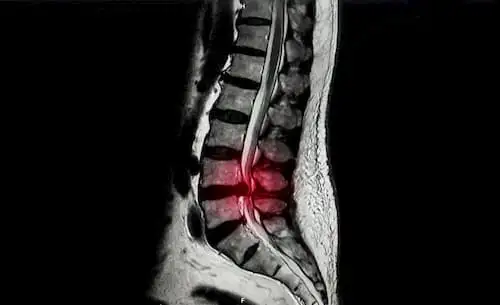

Косой поясничный межтеловой спондилодез с передней винтовой или задней педикулярной фиксацией: сравнение методов лечения дегенеративных заболеваний поясничного отдела позвоночника

Дегенеративные заболевания поясничного отдела позвоночника представляют собой серьезную проблему для здравоохранения, что стимулирует поиск передовых хирургических подходов. Примером перспективного хирургического подхода является косой поясничный межтеловой спондилодез (OLIF), но остается открытым вопрос о том, какая из двух техник эффективнее: OLIF с передней винтовой фиксацией (OLIF-AF) или OLIF с задней педикулярной фиксацией (OLIF-PF). Цель данного исследования состояла в сравнении эффективности этих двух техник.